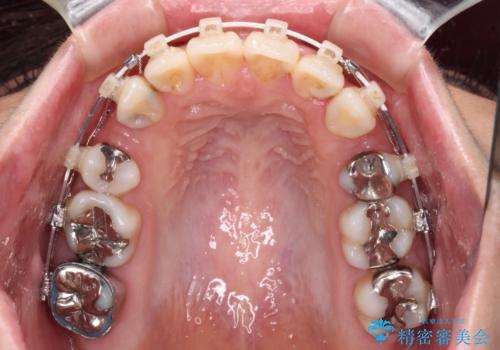

- 矯正装置

- 審美装置

- 口元の突出感と奥歯の欠損を気にして来院された患者様です。

口元の突出感改善には、上下左右の第一小臼歯4本を抜歯し、奥歯の欠損部には矯正治療の途中でインプランを埋入していくこととしました。

矯正治療の後半にインプラント埋入を行うことで、トータルの治療期間を短縮することができました。